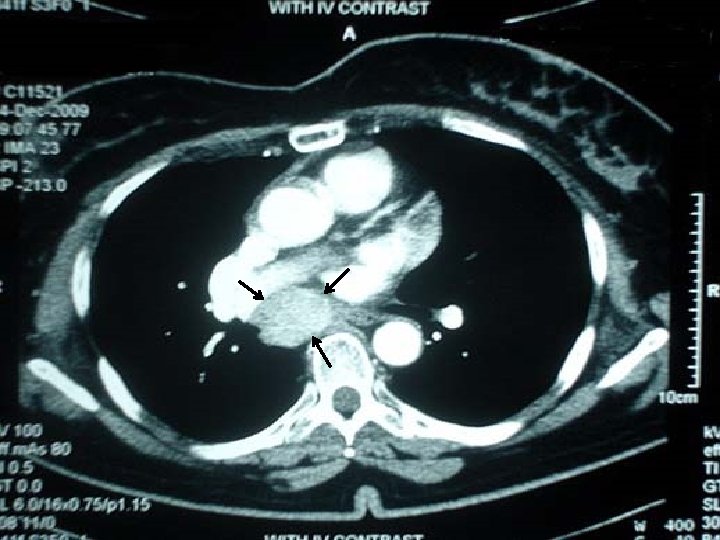

Ø A 53 Y. O lady was referred to us because of acromegalic features. Ø Her work up in another hospital revealed high IGF 1, and unsuppressed GH after glucose challenge. Ø Her pituitary MRI was interpreted as normal in 2 occasions. Ectopic acromegaly was highly suspected.

Ø Histopathologic evaluation revealed the mass is indeed a Paraganglioma. Ø IHC was positive for chromogranin

IHC showed positivity for GHRH.